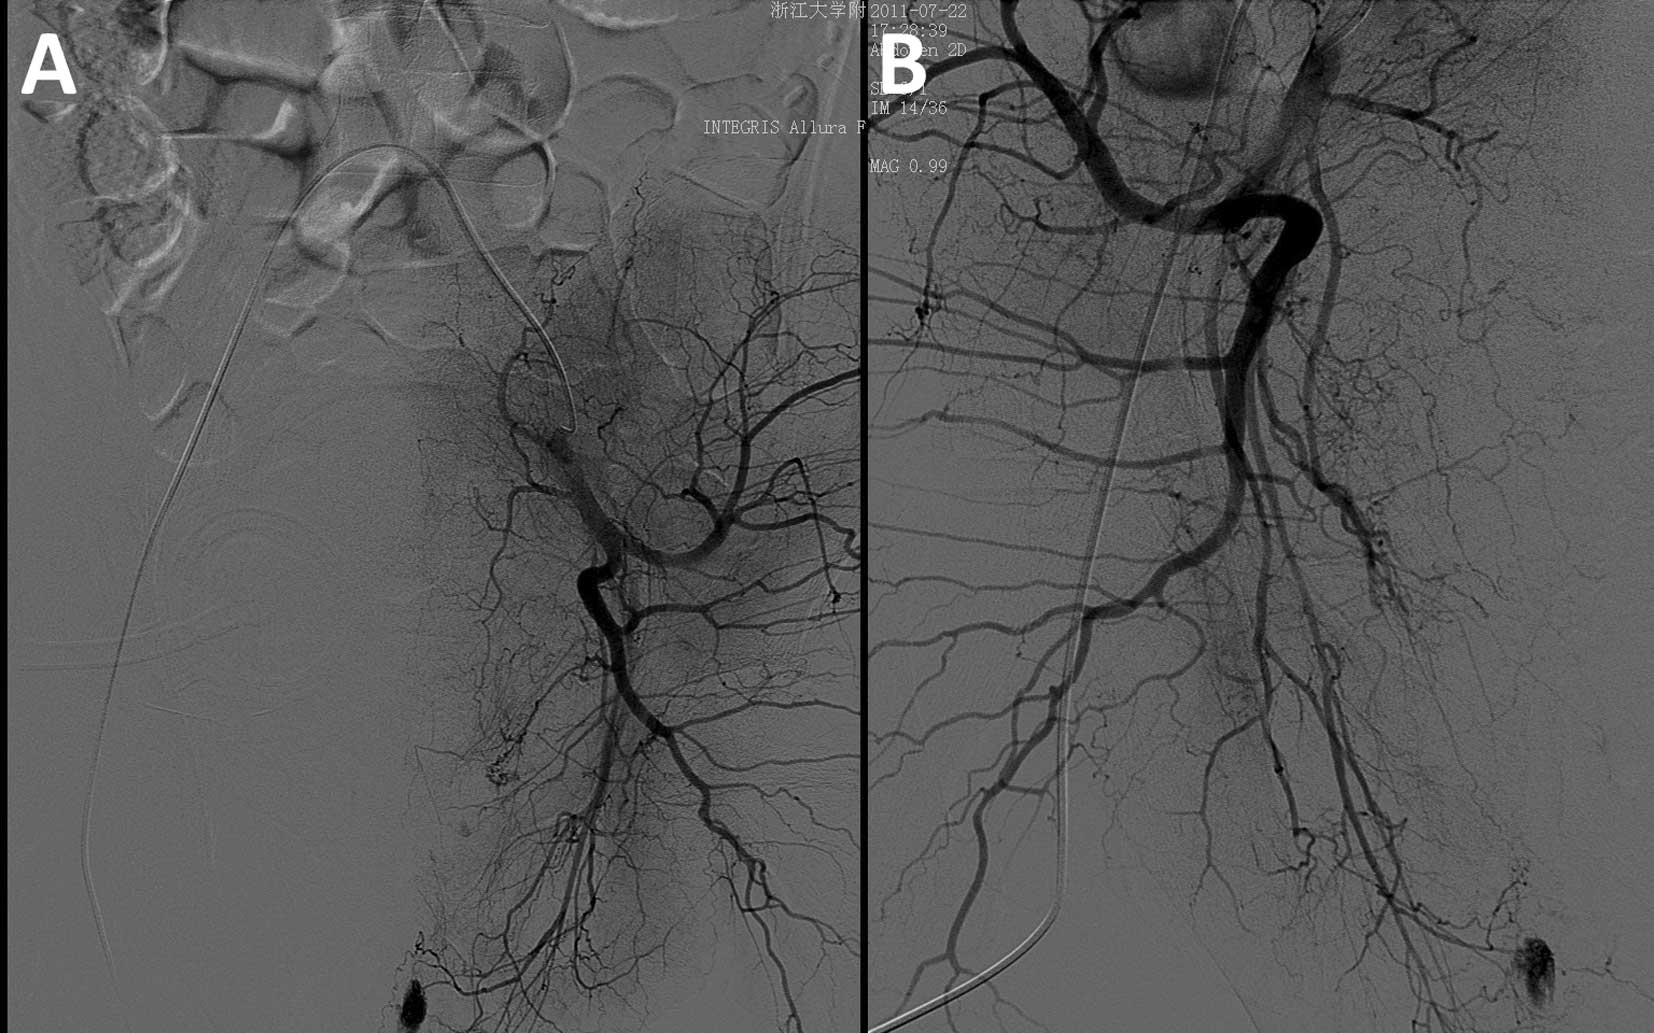

Хирургические процессы при эмболизации гемангиомы на фото

Раздел: Снимки-откровения